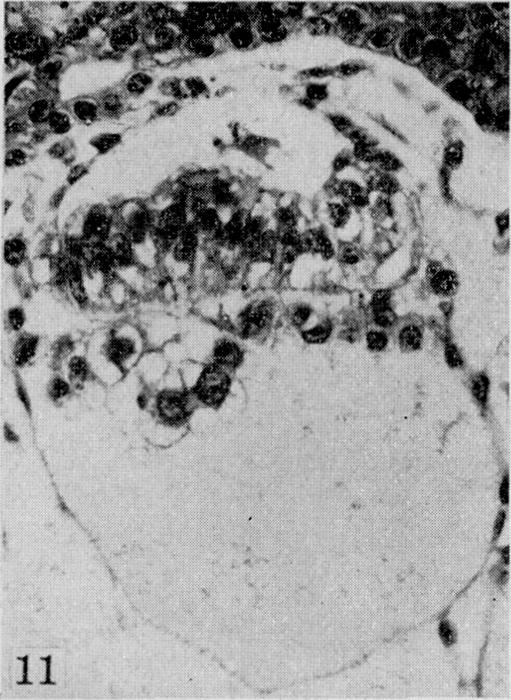

On the development of the amnion and exoccelomic membrane in the previllous human ovum.

Yale J Biol Med. 1945 Dec;18(2):107-15.